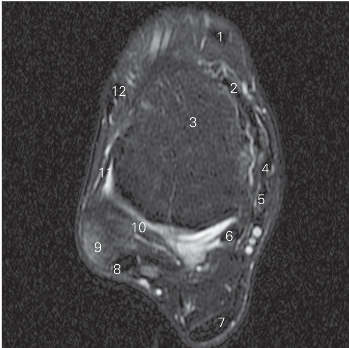

图5-37 经踝关节下方的横断层MR T2WI FS

1 胫骨前肌 tibialis anterior 2 关节囊 joint capsule

3 距骨 talus 4 胫骨后肌 tibialis posterior

5 趾长屈肌 flexor digitorum longus 6

长屈肌 flexor hallucis longus

7 跟腱 tendo calcaneus

8 腓骨长、短肌 peroneus longus and brevis

9 外踝 lateral malleolus

10 距腓后韧带 posterior talofibular ligament

11 距腓前韧带 anterior talofibular ligament

12 趾长伸肌 extensor digitorum longus